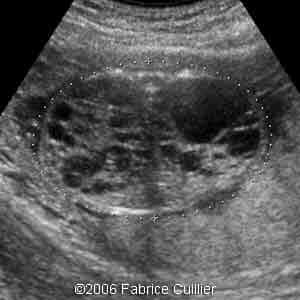

3D coronal view at 17 weeks

3